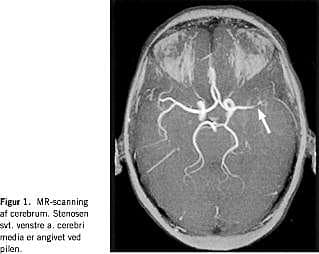

En 42-årig, tidligere rask kvinde af dansk afstamning blev indlagt på mistanke om apopleksi. Forud for indlæggelsen havde patienten haft hovedpine og tilbagevendende tilfælde af 1-2 minutters varighed med følelsesløshed og tyngdefornemmelse i de højresidige ekstremiteter, efterfulgt af nedsat kraft og styringsbesvær. Der var ingen familiære dispositioner for tromboemboliske sygdomme. Tobaksforbruget var på 10-15 cigaretter daglig. Hun anvendte ikke hormonel antikonception. Objektivt fandtes højresidig central facialis parese samt nedsat kraft i højre underekstremitet. Der påvistes leukocytose, uden C-reaktivt protein eller sænkningsreaktionsforhøjelse. En magnetisk resonans (MR)-skanning af cerebrum, et elektroencefalogram og en spinalvæskeundersøgelse viste alle normale forhold, og efter 12 dages indlæggelse blev patienten udskrevet. Hun blev genindlagt fem uger senere med ekspressiv afasi og kramper i begge underekstremiteter. En computertomografi af cerebrum viste infarkt ved venstre capsula interna. En ultralydundersøgelse af halskar og hjerte viste, at de var uden embolikilder. På mistanke om postinfarkt epilepsi blev patienten sat i behandling med oxcarbazepin. I efterforløbet fik hun urtikaria og Coombs negative hæmolyse (medikamentelt betinget?). oxcarbazepin blev erstattet med clonazepam, og der indledtes højdosis prednisolonbehandling. Objektivt fandtes nu mislyd under begge claviculae. Blodtrykket var normalt (120/70) på begge arme. På mistanke om TA blev der foretaget MR-angioskanning af cerebrum og halskar, hvorved der påvistes stenose på hhv. venstre a. cerebri media (Figur 1 ) og venstre a. carotis communis ved afgangen fra aorta (Figur 2 ). Ved trombofiliudredning fandtes patienten homozygot for FVL, hvorfor antikoagulantiabehandling blev iværksat. Patienten blev overflyttet til reumatologisk afdeling, hvor der efterfølgende fandtes forskelle i blodtrykket (højre: 139/84, venstre: 118/75). Efter yderligere tre ugers steroidbehandling hørtes mislydene ikke længere.